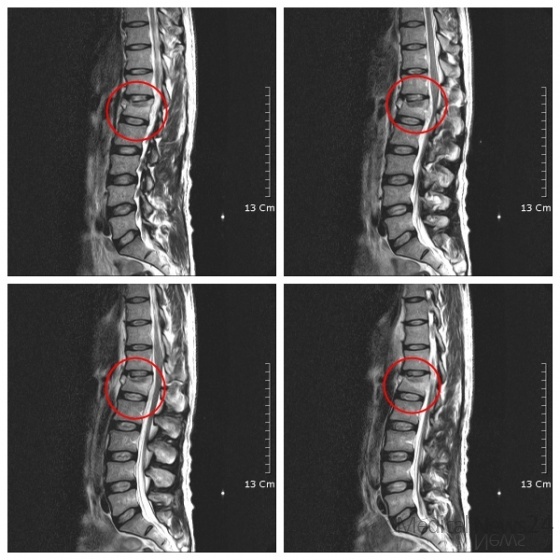

< 우즈베키스탄 환자의 제1요추 방출성 압박골절에 실시한 척추수술 및 골이식술 방사선 영상>